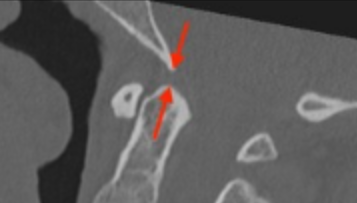

Image Type Cervical Spine X-Ray CT Scan MRI Scan Atlantodental Interval (ADI) Basion–Axial Interval (BAI) Basion–Dens Interval (BDI) Canal Occupying Ratio (COR) Clivo-Axial Angle Facet Joint Overlap (Percent Overlap Method) Facet Joint Step-Off/Dislocation Grabb-Oakes Measurement (pB - C2 line) Occipital Condyle–C1 Interval (CCI) Posterior Atlantodental Interval (PADI) Power’s Ratio Sagittal Vertical Axis (SVA) Segmental Angle Translation on Sagittal Reconstruction